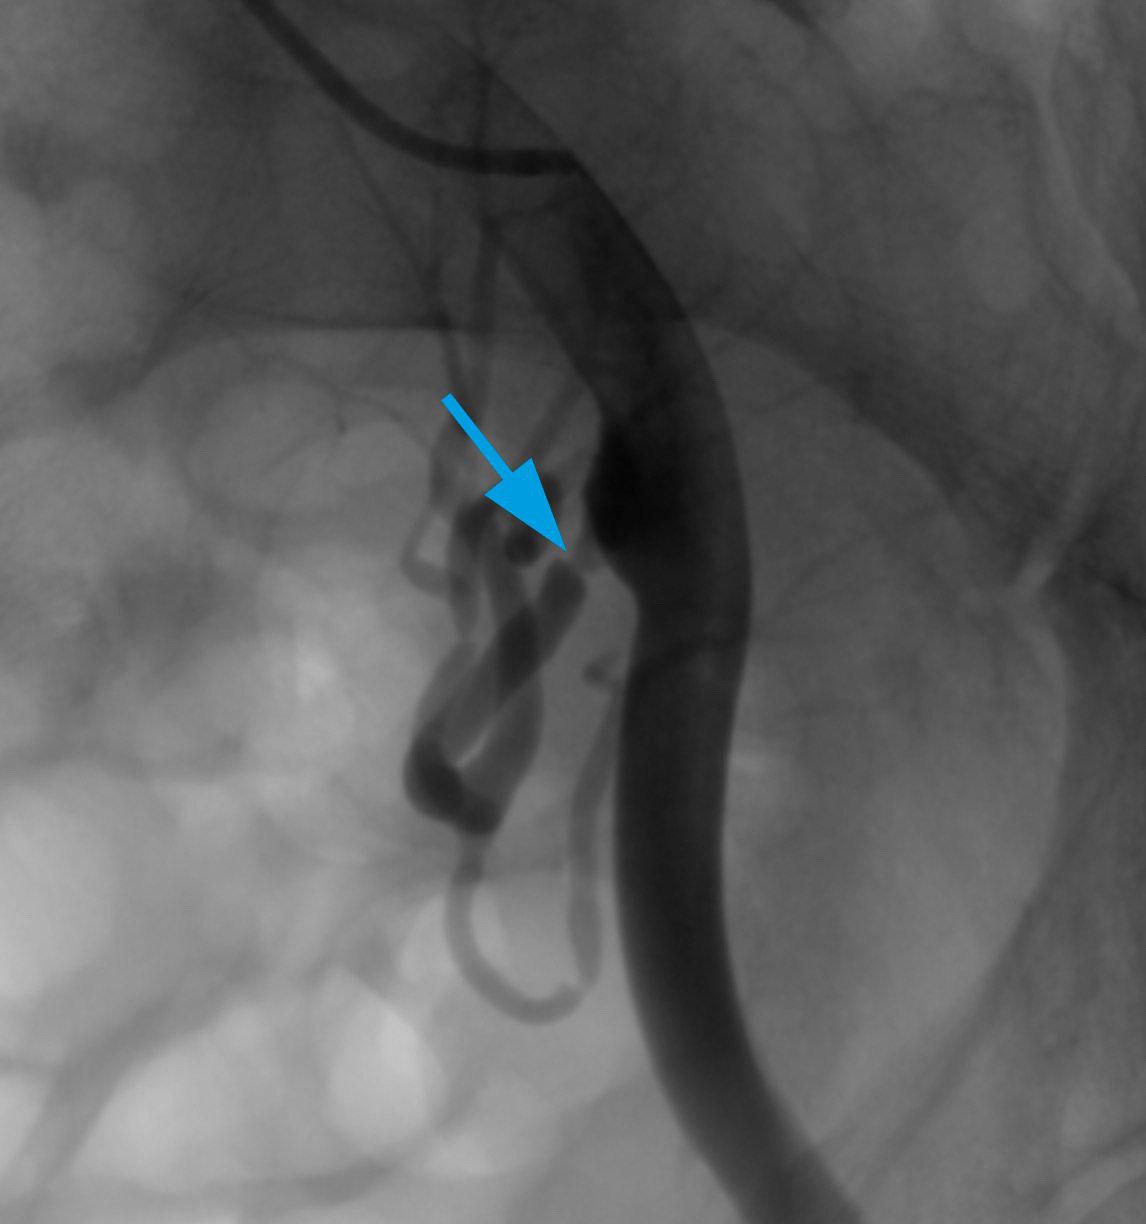

Операцию пациенту проводил Д. В. Фетцер под местной анестезией доступом через правую плечевую артерию. На ангиограммах стеноз в проксимальной трети почечной артерии был визуализирован и начата операция (рис. 1).